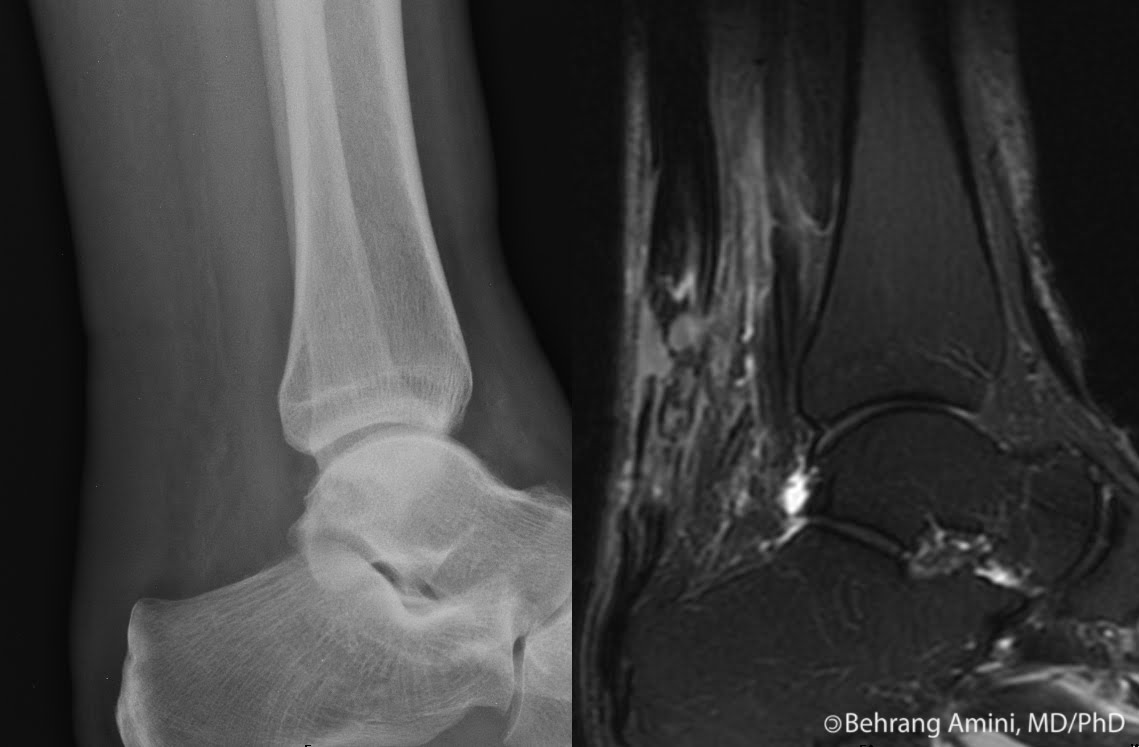

Achilles Tendon Injury X Ray . There is a complete tear of achilles tendon approximately 6 cm away from the insertion site. The radiographs demonstrated obliteration of kager's fat pad, a finding highly suspicious for an achilles tendon rupture (figures 1 and 2). Achilles tendon ruptures are common tendon injuries that occur due to sudden dorsiflexion of a plantarflexed foot, most commonly associated with sporting events. Evaluation of heel pain can be clinically challenging, and. The achilles tendon originates in. The gap between the two edges. There was tenderness at the lateral malleolus, and ankle range of motion (rom) couldn't be elicited due to injury. 1 kager's fat pad, located. Therefore, we review the anatomy, mr imaging findings, and pathologic findings in an attempt to develop a systematic nomenclature. Achilles tendon tears are the most common ankle tendon injuries, with microtears to full thickness tendon tears of the achilles tendon and are most commonly seen secondary to.

Investigating the Validity of Soft Tissue Signs on Lateral Ankle XRay Achilles Tendon Injury X Ray Evaluation of heel pain can be clinically challenging, and. The radiographs demonstrated obliteration of kager's fat pad, a finding highly suspicious for an achilles tendon rupture (figures 1 and 2). There is a complete tear of achilles tendon approximately 6 cm away from the insertion site. Therefore, we review the anatomy, mr imaging findings, and pathologic findings in an attempt. Achilles Tendon Injury X Ray.

melbournemrileftachillestendonrupture8 MRI at Melbourne Achilles Tendon Injury X Ray The gap between the two edges. 1 kager's fat pad, located. Therefore, we review the anatomy, mr imaging findings, and pathologic findings in an attempt to develop a systematic nomenclature. There is a complete tear of achilles tendon approximately 6 cm away from the insertion site. Achilles tendon ruptures are common tendon injuries that occur due to sudden dorsiflexion of. Achilles Tendon Injury X Ray.